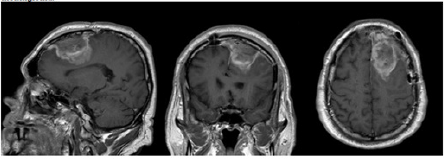

Image study: Cranial MRI showed a left parasagittal frontal lesion compatible with a meningioma (Figure 1).

Figure 1: Brain MRI at admission showing a large mass involving the left frontal region, suggestive of a giant meningioma.